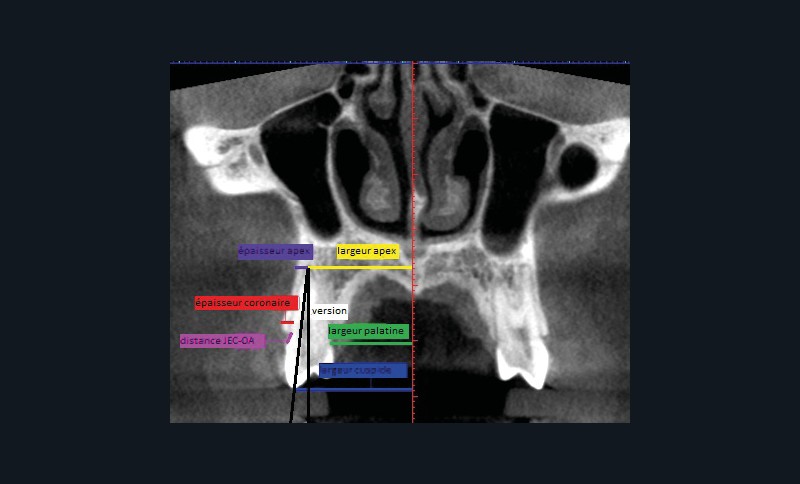

Sept mesures ont été réalisées pour quantifier le déplacement dentaire et les modifications alvéolaires (fig. 1 et 2). de chaque côté :

– largeur au niveau de l’apex ;

– largeur palatine mesurée au niveau du collet ;

– largeur au niveau de la cuspide vestibulaire ;

– quantité de version ;

– épaisseur de l’os alvéolaire à l’apex ;

– épaisseur de l’os alvéolaire coronaire mesurée à 2 mm apicalement à la crête ;

– distance jonction amélo-cémentaire-crête alvéolaire.